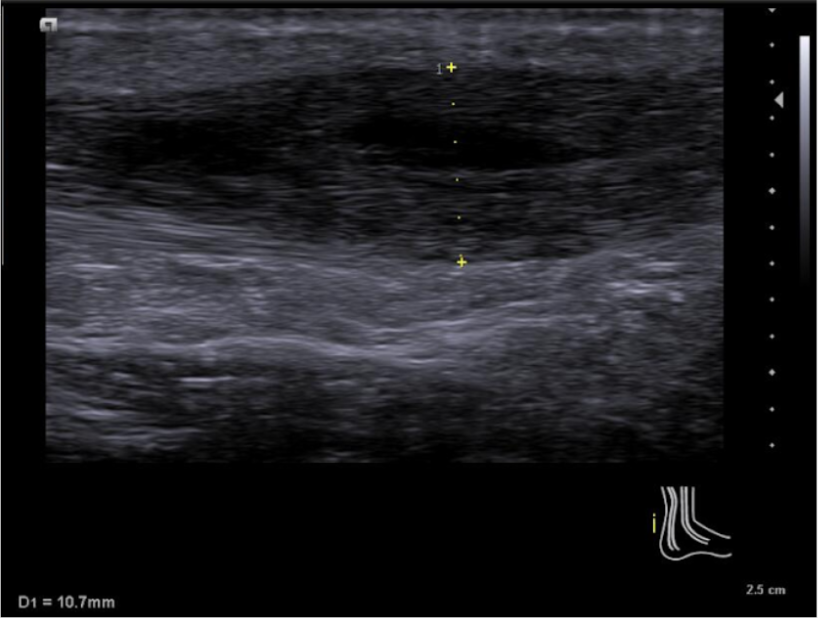

Se emplea sonda lineal L10-5v de forma longitudinal al tendón de aquiles, observando una zona anecoica en interfase del tendón a unos 7 cm de la inserción calcánea, con pérdida de continuidad del patrón fibrilar de las fibras tendinosas y aumento del grosor de este. No aumento de captación en Doppler.